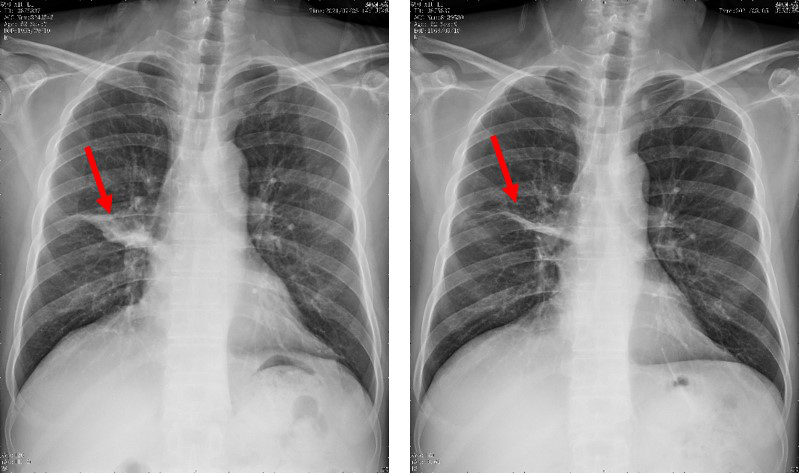

1个月后,患者症状基本消失,复查胸片显示肺部病变较前明显吸收好转(图4)。出院后患者继续口服泊沙康唑,门诊随诊。

图4入院时胸片显示右肺病变;治疗1个月后复查胸片显示右肺病变明显吸收好转